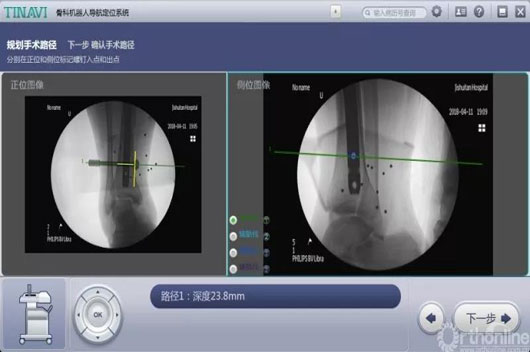

这两台手术划分是机械人辅助后踝骨折闭合复位空心钉牢靠术和机械人辅助距下枢纽融合术。。。。。。。特殊是机械人辅助距下枢纽融合术,,,,,敌手术的精准度要求很是高。。。。。。。

古板手术要领需要大面积袒露患部,,,,,导针重复操作确定位置、同时多次透视,,,,,手术时间长、患者损伤大,,,,,并发症几率高。。。。。。。而现在只需要把融合的枢纽面举行处置惩罚后,,,,,装置好骨科导航机械人,,,,,把伤口用敷料盖好后,,,,,在病人体外用机械人做妄想,,,,,并凭证妄想精准置入螺钉。。。。。。。病人真正的手术时间大大缩短,,,,,袒露的伤口小、辐射少、手术效果抵达最佳。。。。。。。

术中妄想远端锁钉位置